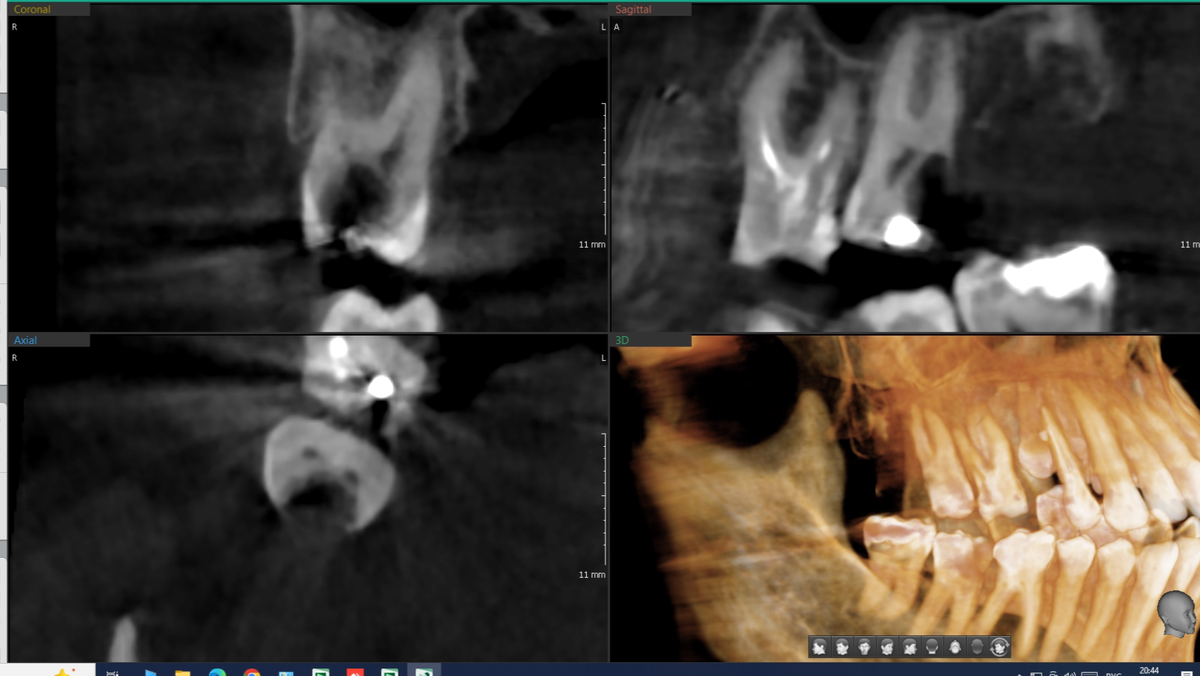

Конец весны 2025 года. Первая консультация у ортопеда, в тот же день - у хирурга.

Проблема - правый верхний жевательный сегмент требует комплексного лечения.

Верхняя челюсть, правая сторона, жевательный сегмент

Середина июня. Зуб 1.7 - на вид, явный кандидат на удаление (на фото он крайний, половина коронковой части отсутствует). Огромный кариозный очаг, переходящий на корень, нерв мёртв 100%:

Зуб 1.7 до лечения